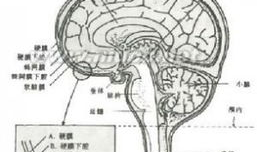

脑膜刺激征检查视频,直观解析临床诊断技巧

你有没有想过,去医院看病的时候,医生有时候会给你来点“特殊待遇”?比如说,给你做个脑膜刺激征检查。这听起来是不是有点陌生?别急,...